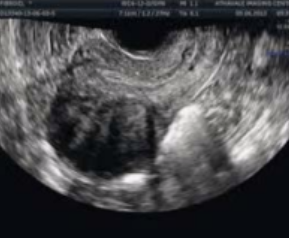

What type of fibroid is depicted in this image?

a. Intramural

b. Submucosal

c. Subserosal

d. Pedunculated

Subserosal

Where is this fibroid located in the uterus?

a. Anterior

b. Posterior

c. Cervical

d. Fundal

Anterior

Is this image endovaginal or transabdominal?

a. Endovaginal

b. Transabdominal

Endovaginal